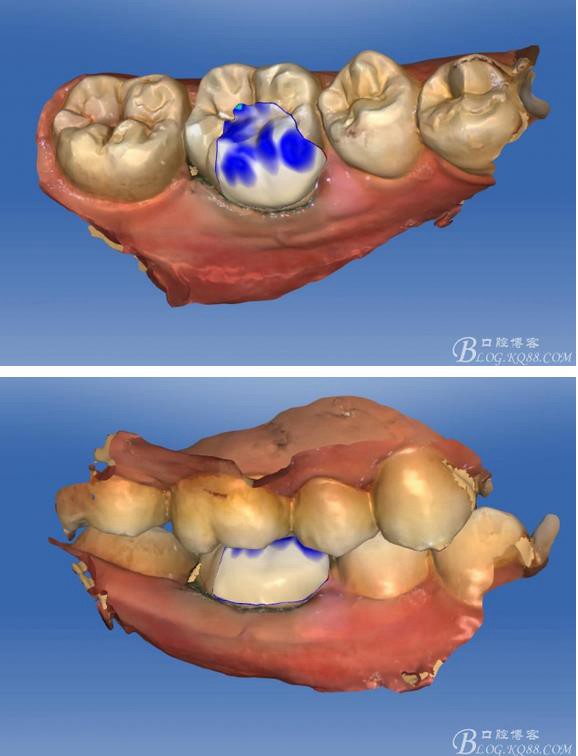

畫線是最關鍵的,線畫不好制出的修復體會出現(xiàn)邊緣缺損 或多 或少,醫(yī)生和技術(shù)配合

掃描 畫線 準備研磨